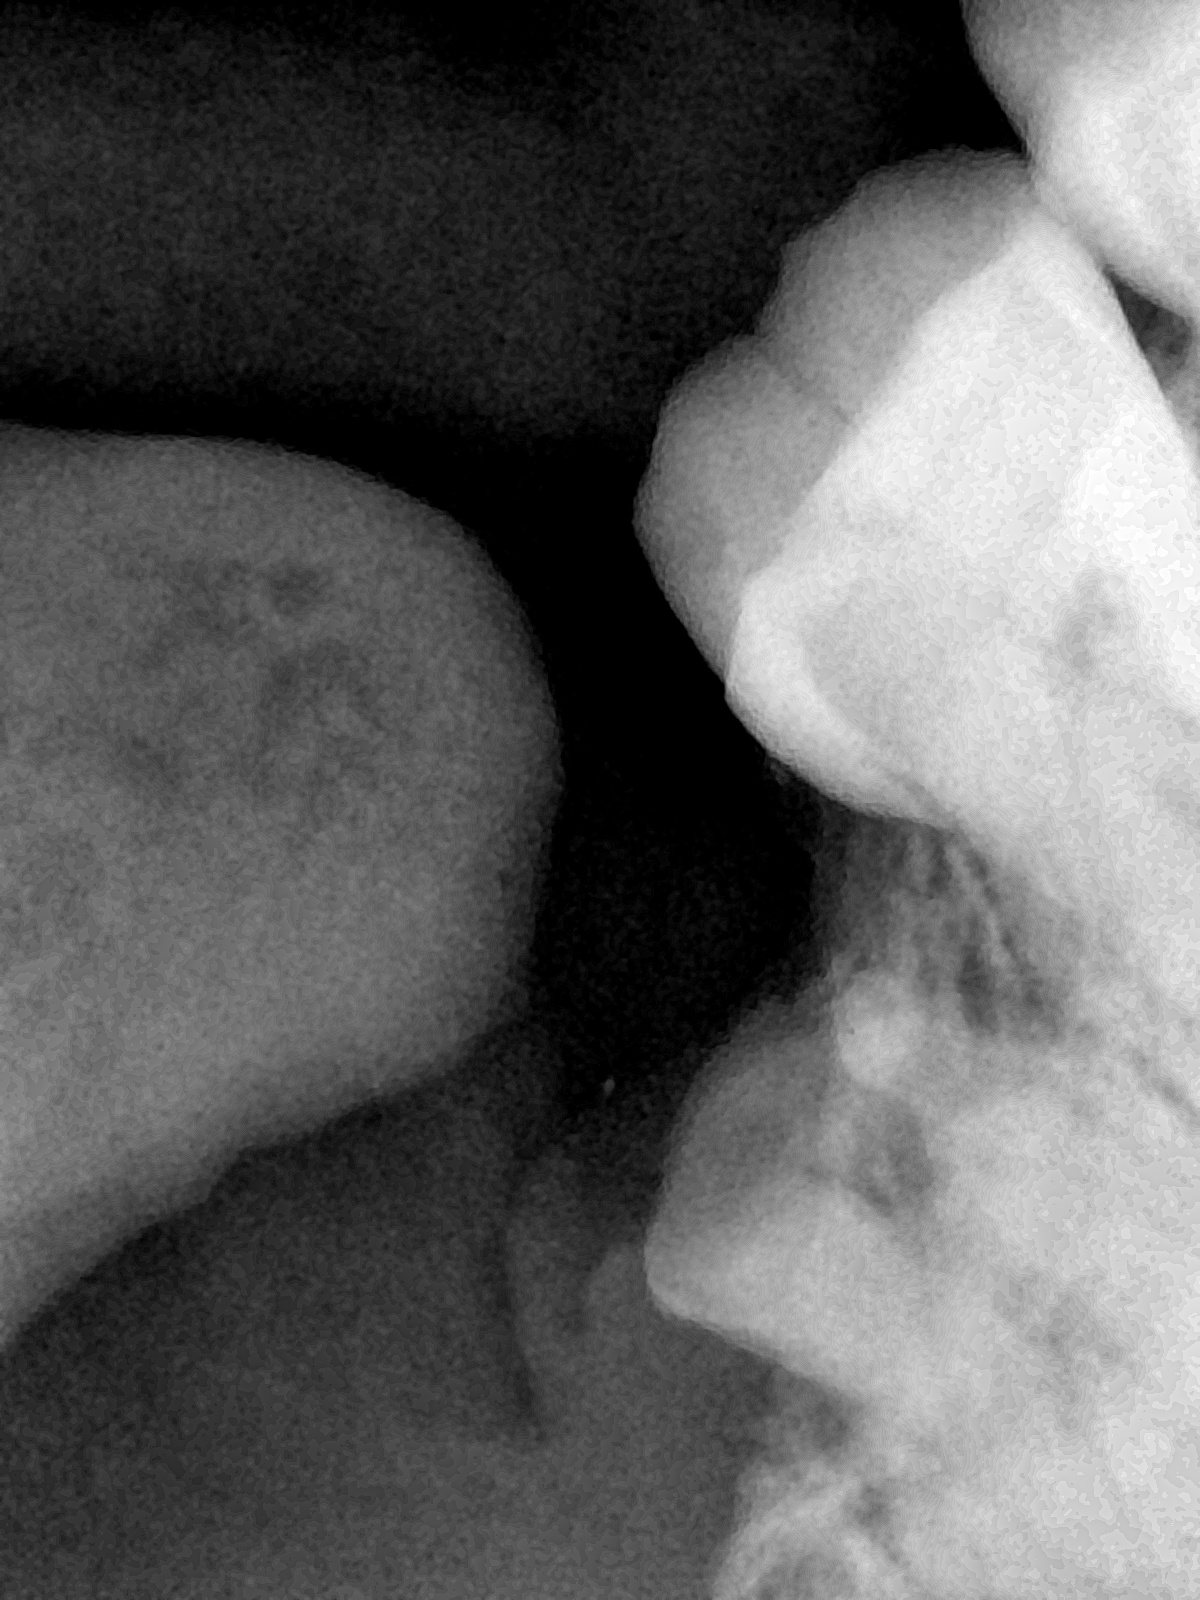

CR/DR 牙齿分割阶段记录

当前进展

- 完成了 CR/DR 牙齿相关分割训练

- 当前结果已经达到阶段预期,但仍有细节问题需要继续处理

相关测试

遇到的问题

- 训练过程中出现过 mask 下移问题

- 部分结果会出现 box 填充异常

- mask 边缘仍然有比较明显的锯齿感

第二版算法问题测试